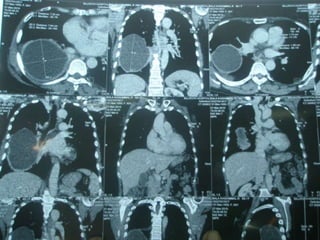

a.2. Tomodensitométrie thoracique

• Pas indispensable au diagnostic de kyste

hydatique du poumon

• Utile dans le bilan lésionnel pré opératoire.

• Analyse paroi du kyste, topographie, rapports

avec bronches et structures vasculaires.